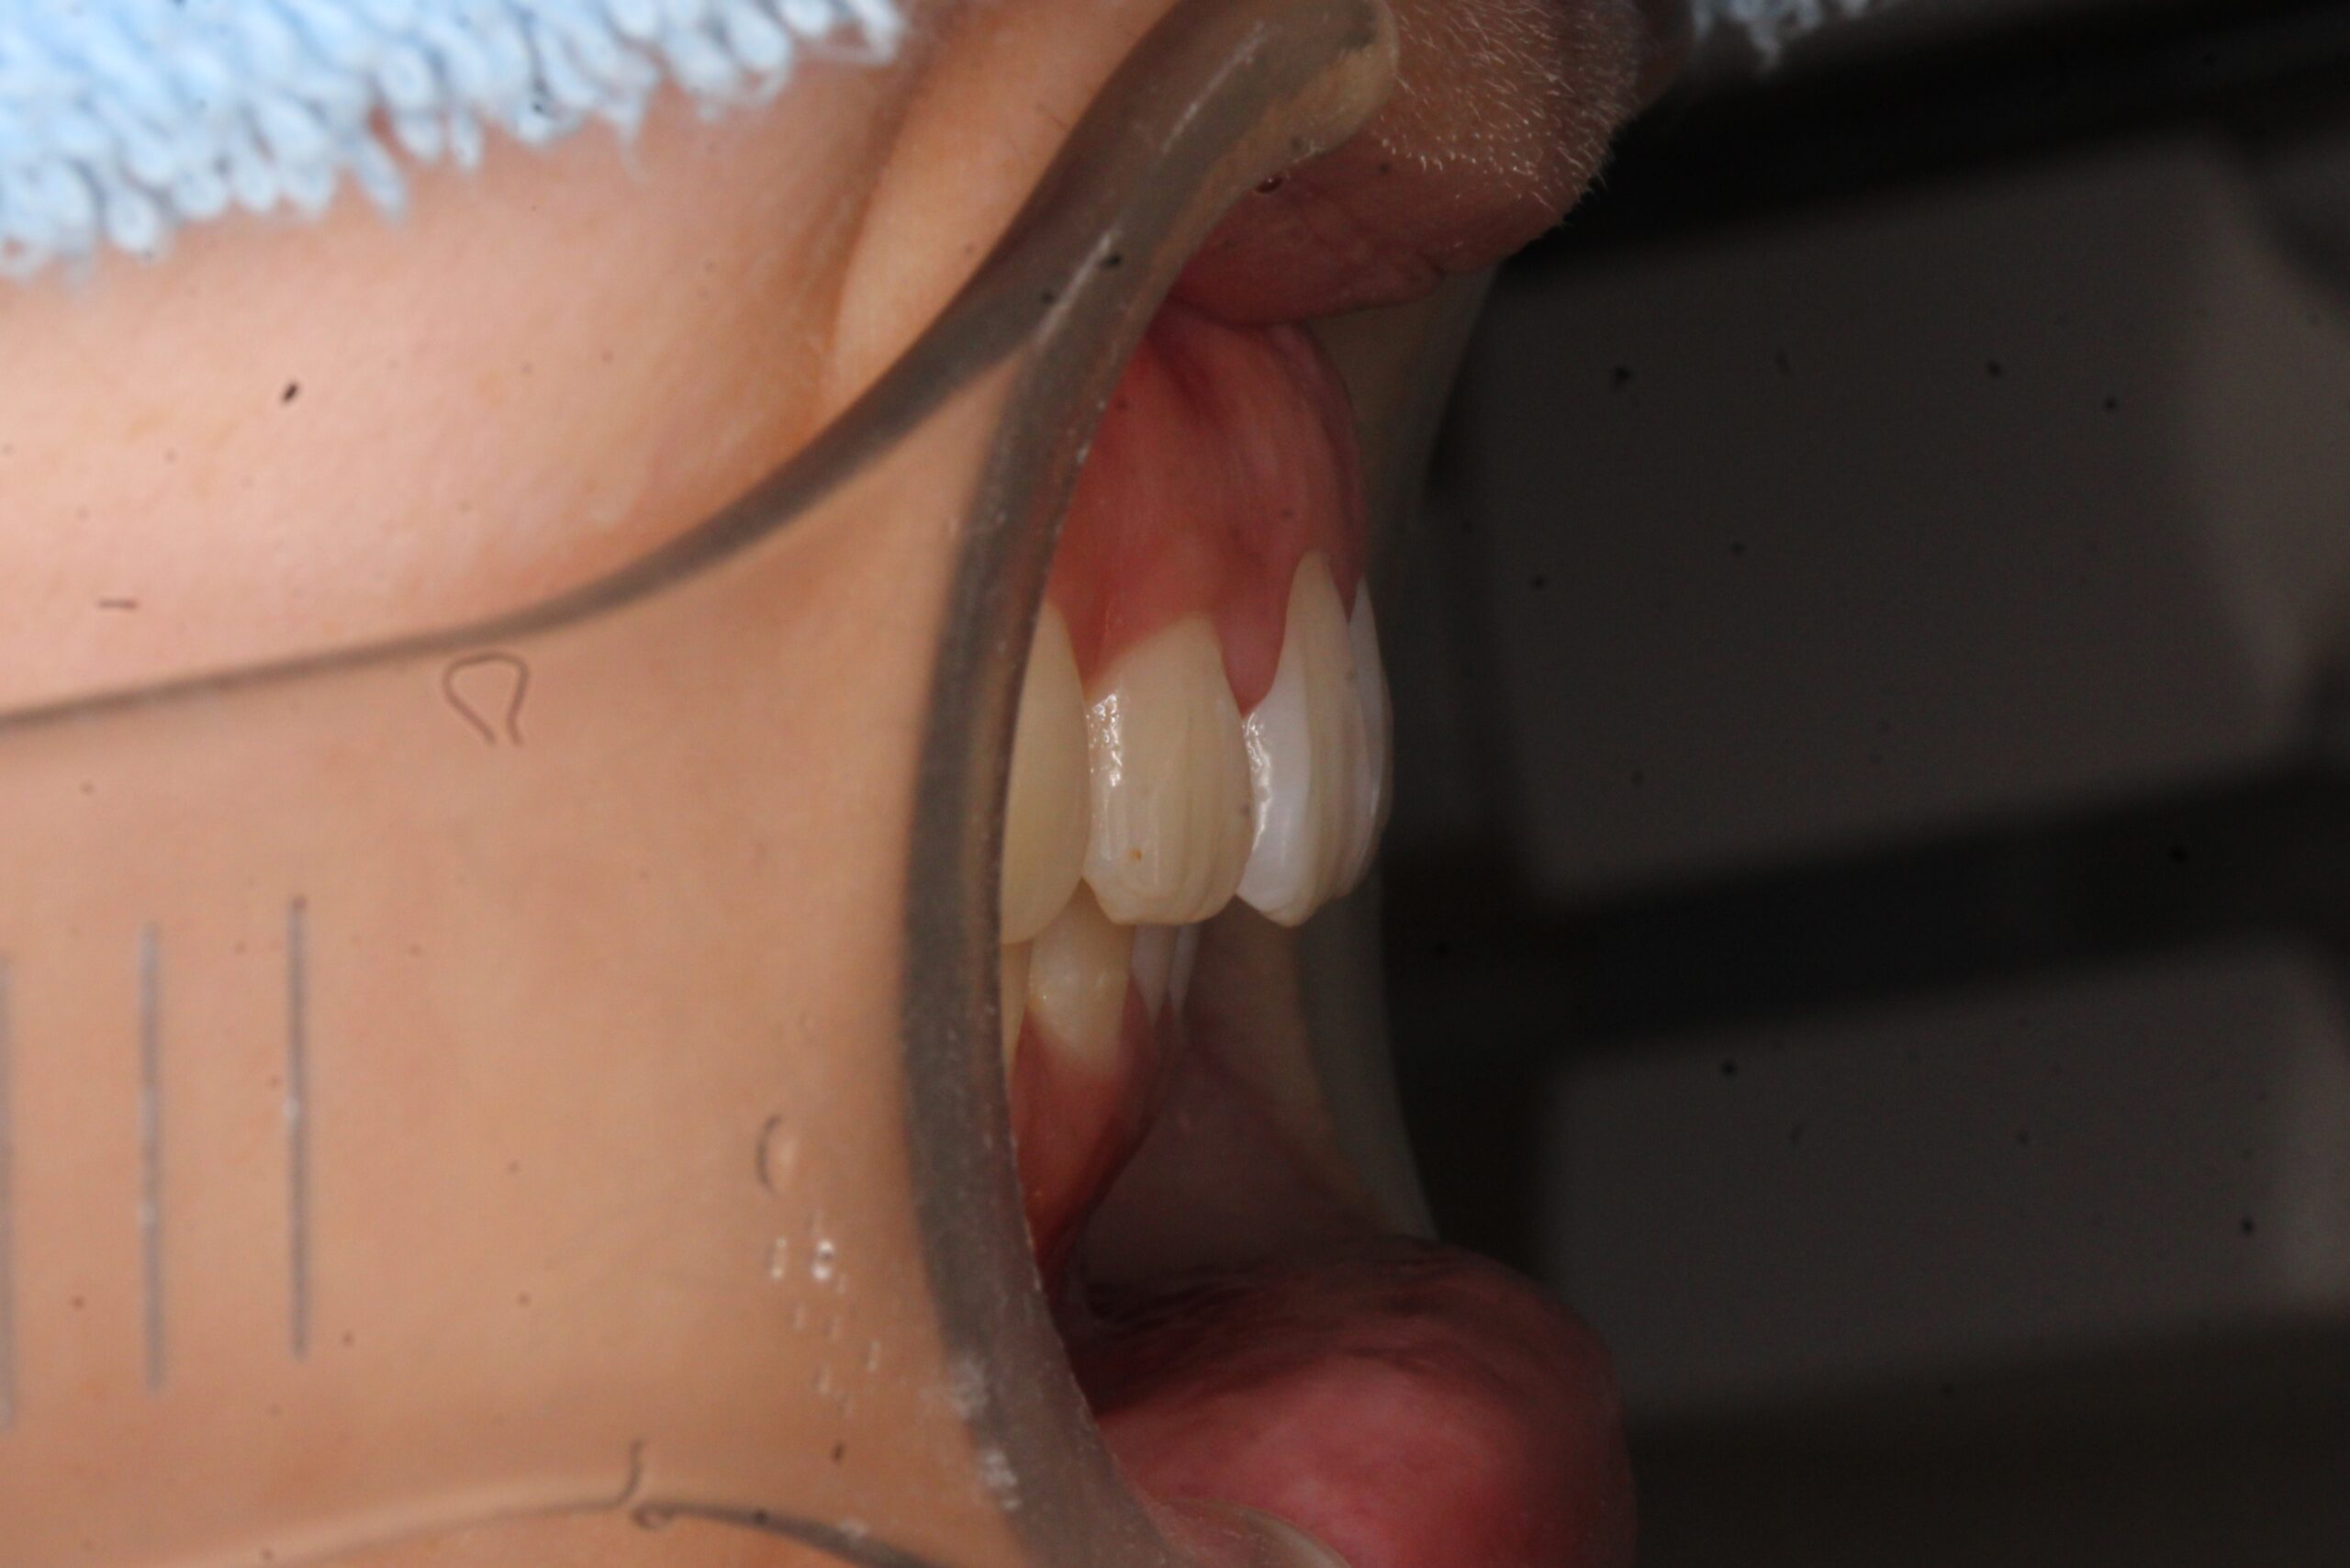

矯正術前:オーバージェット

矯正術後:オーバージェット